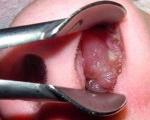

• Эндоскопия носовой полости. Риноскопия позволяет визуализировать полость носа, обнаружить полипы, оценить их размер, количество. Образование полипоза серо-белого цвета, мягкой и эластичной консистенции, безболезненно при надавливании. Внешне полипы могут напоминать горошину, грибовидный нарост или гроздь винограда.

Эндоскопия носовой полости ребенку.